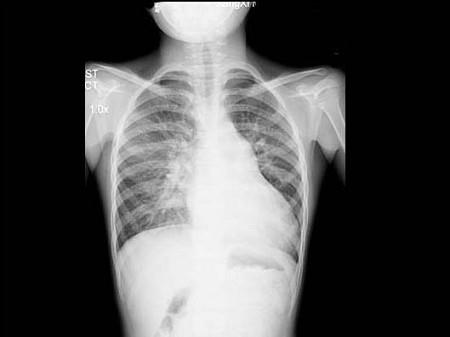

问题 5岁男孩,诊断先心病室间隔缺损,拍胸部正位片如图所示,你认为下列关于肺部正确的结论是 ( )

选项 A、间质性肺水肿 B、肺充血 C、正常肺 D、肺泡性肺水肿 E、肺淤血

答案 B